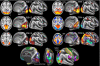

Resting-state functional magnetic resonance imaging has become a powerful tool for the study of functional networks in the brain. Even "at rest," the brain's different functional networks spontaneously fluctuate in their activity level; each network's spatial extent can therefore be mapped by finding temporal correlations between its different subregions. Current correlation-based approaches measure the average functional connectivity between regions, but this average is less meaningful for regions that are part of multiple networks; one ideally wants a network model that explicitly allows overlap, for example, allowing a region's activity pattern to reflect one network's activity some of the time, and another network's activity at other times. However, even those approaches that do allow overlap have often maximized mutual spatial independence, which may be suboptimal if distinct networks have significant overlap. In this work, we identify functionally distinct networks by virtue of their temporal independence, taking advantage of the additional temporal richness available via improvements in functional magnetic resonance imaging sampling rate. We identify multiple "temporal functional modes," including several that subdivide the default-mode network (and the regions anticorrelated with it) into several functionally distinct, spatially overlapping, networks, each with its own pattern of correlations and anticorrelations. These functionally distinct modes of spontaneous brain activity are, in general, quite different from resting-state networks previously reported, and may have greater biological interpretability.